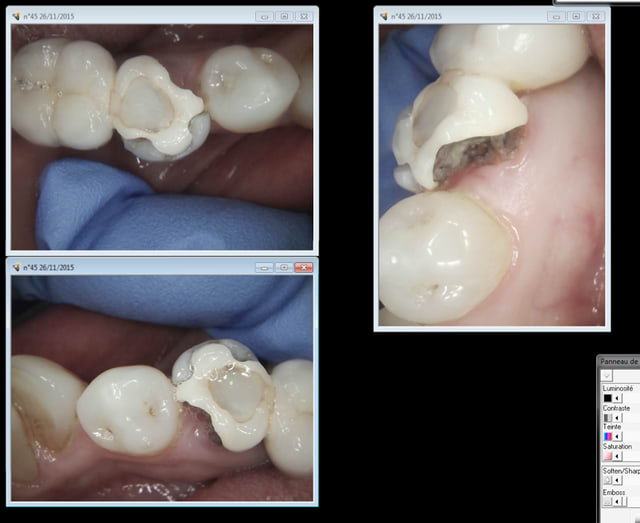

Suivant : 45 cassée ( jadis un onlay support de bridge ? ) Dent gardée vivante puis endo à travers l'onlay je suppose. ca marche moins bien après forcément. -))))